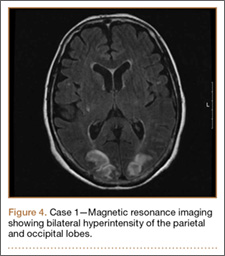

Clinical Presentation. A 51-year-old woman presented to the outpatient clinic with progressive low back pain and decompensation due to degenerative adult scoliosis. Her surgical history was significant for an uneventful Caesarean section. Her medical history was significant for borderline hypertension and obesity (body mass index, 34.4). The radiographic examination showed an S-shaped thoracolumbar curve from T4 to L4 (Figure 5).